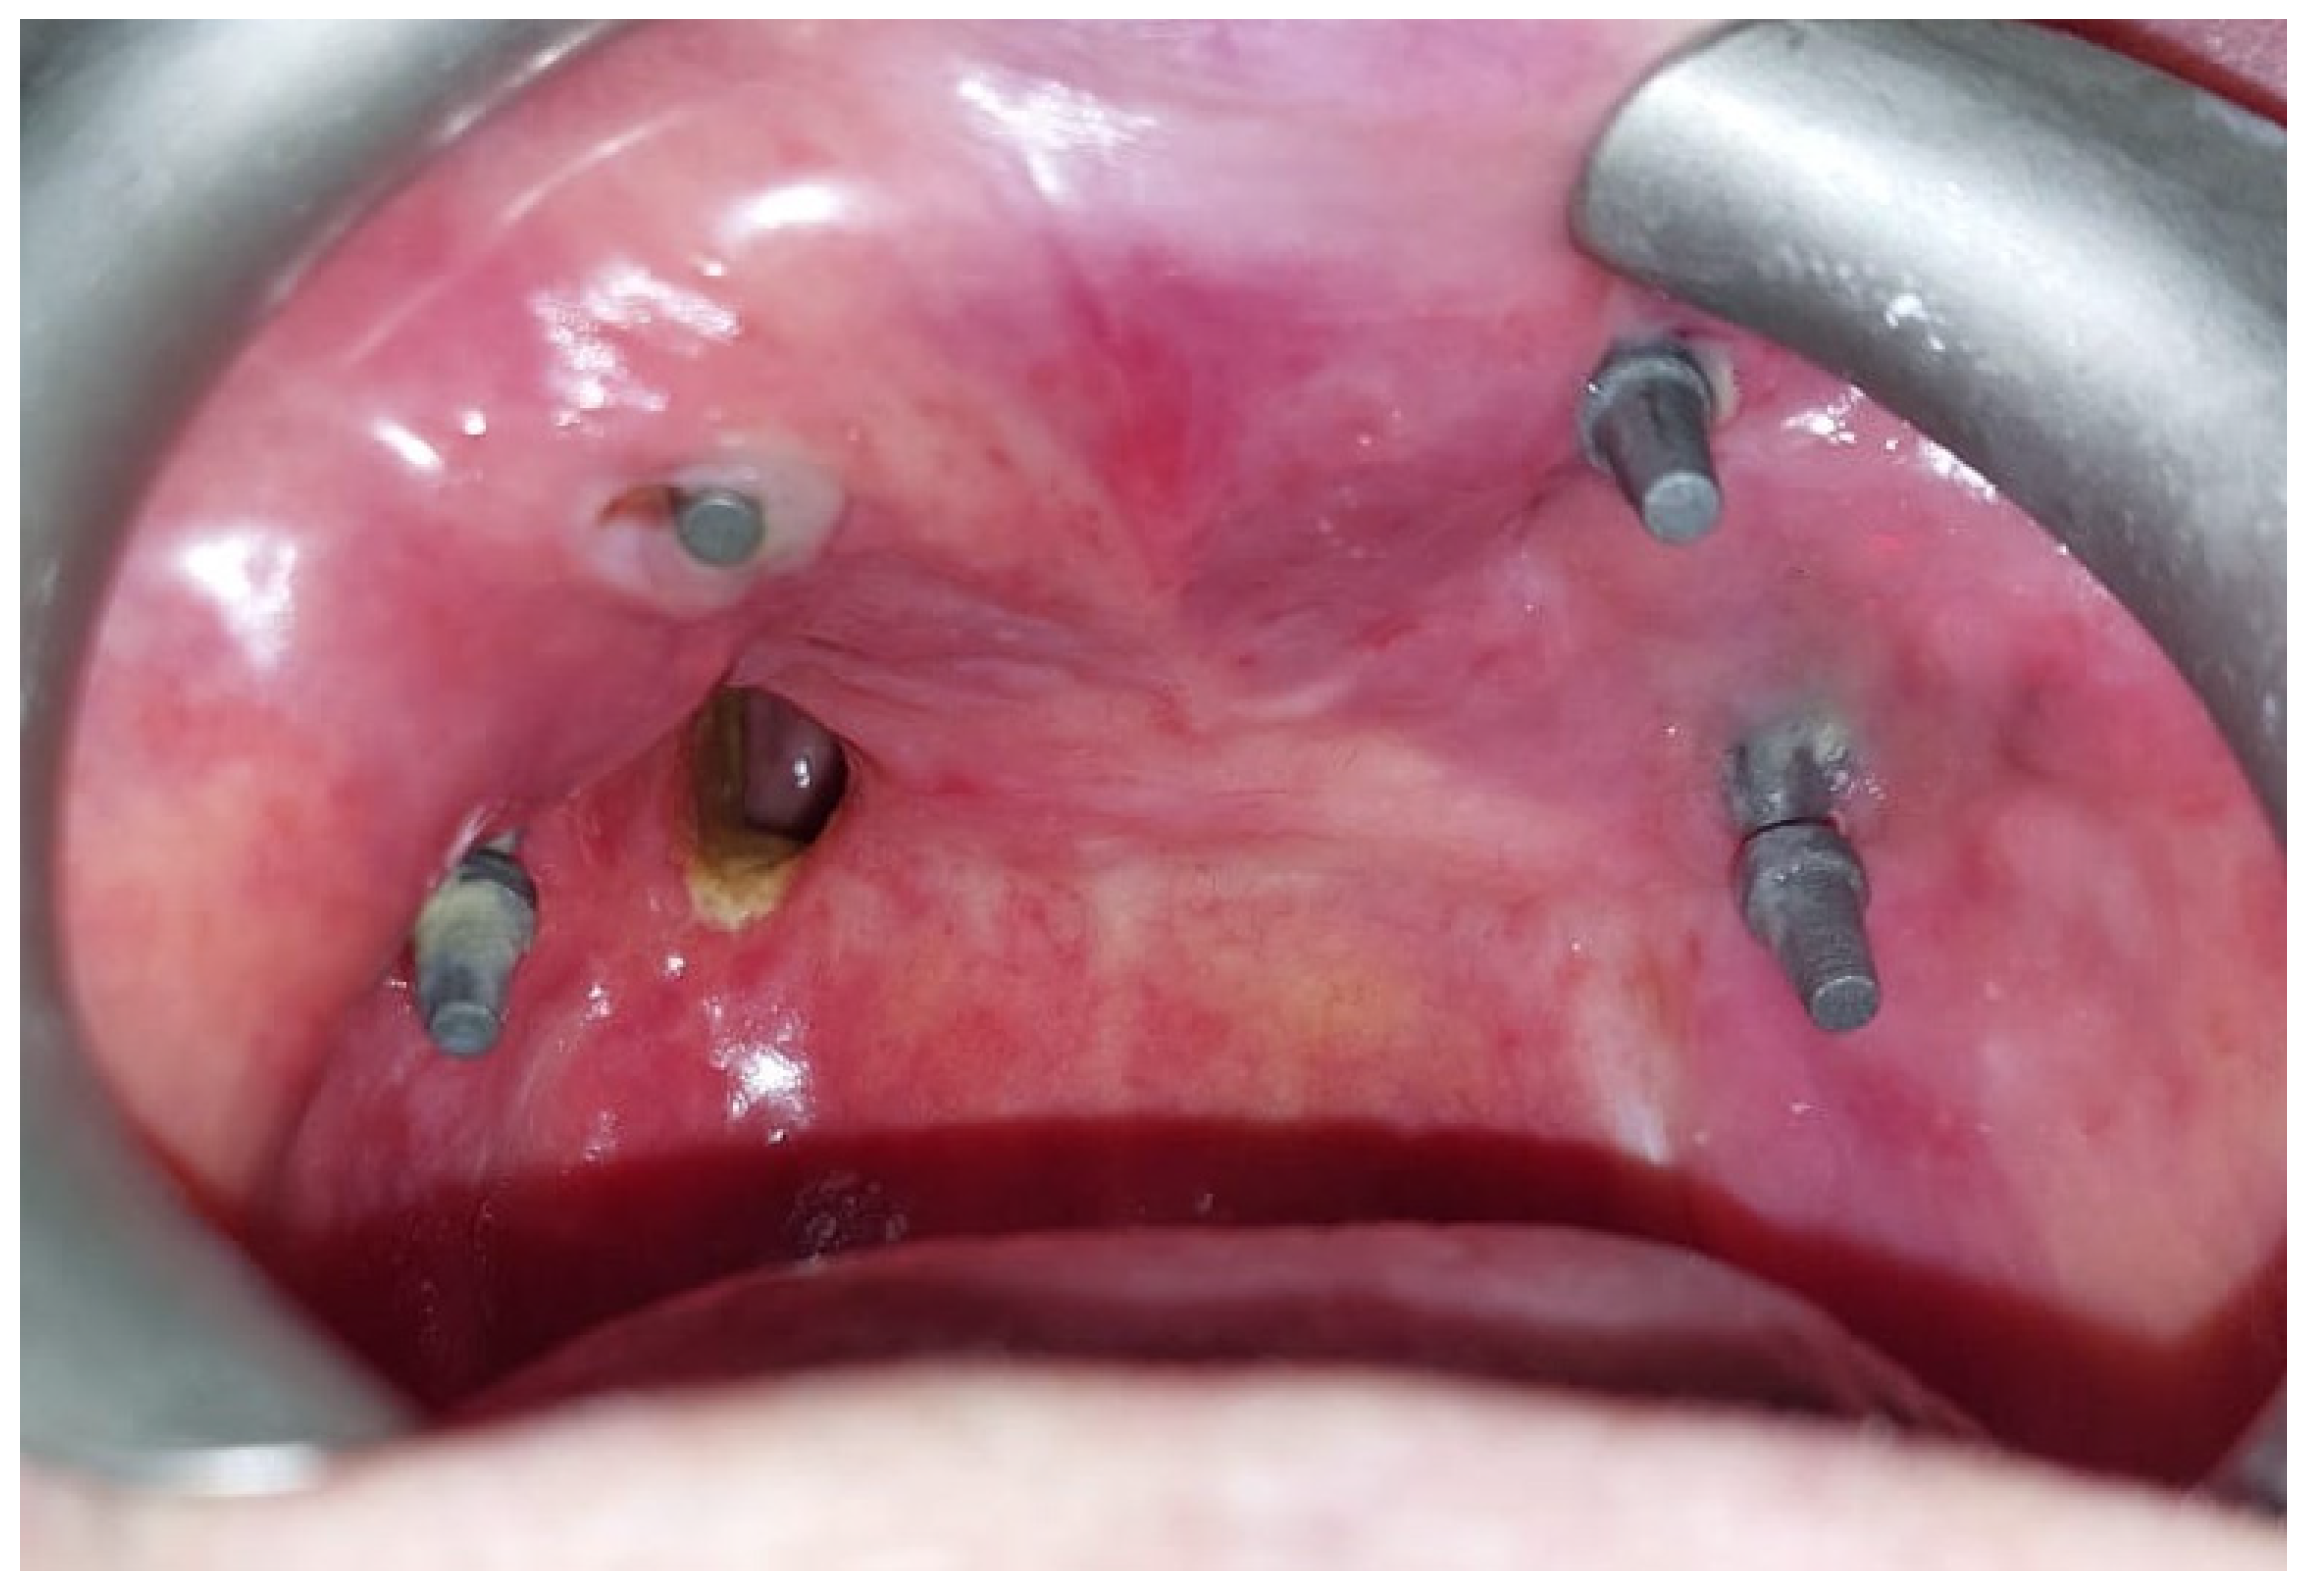

After the complete healing of the surgical wounds, 60 days after surgery, the rehabilitation was completed with the placement of the prosthesis [Figure 8].

Figure 8.

(A) Lower prosthesis. (B) Upper prosthesis. (C) Intraoral view 6 months after the surgery. (D) Oroantral fistula closure with palatal obturator included in the prosthesis.

The oroantral fistula was closed with a palatal obturator included within the prosthesis. The subperiosteal implant provided satisfactory soft tissue support and a proper projection of the middle-third of the face [Figure 9]. No complications occurred in the first six months of follow-up.